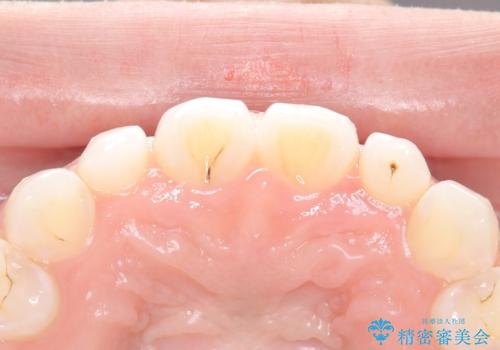

【ダイレクトボンディング】歯を削らずに綺麗にしたい。

- 矯正治療終了後、矮小歯の修復を希望された患者様です。

治療選択肢として、セラミッククラウン、ラミネートベニア、ダイレクトボンディングを提示したところなるべく歯を削りたくないとのことでダイレクトボンディングにて治療を行いました。